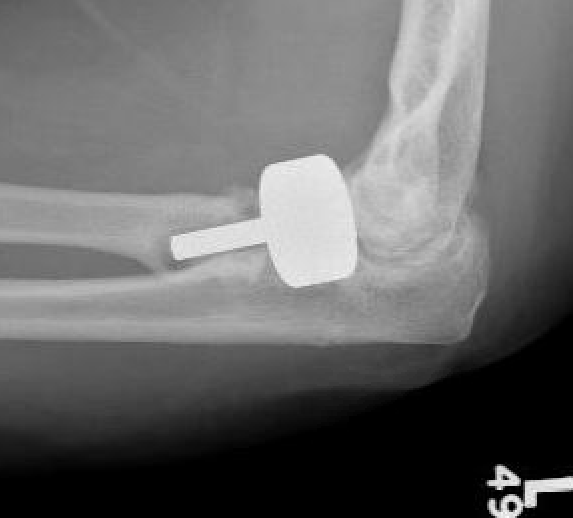

Overstuffing

| Lesser sigmoid notch | Symmetry of ulnohumeral joint |

|---|---|

|

Radial head shoulder articulate with lesser notch

Ensure no gapping of lateral ulnohumeral joint |

- cadaveric study

- increased medial ulno-humeral joint line gapping with overlengthening of 6 or 8 mm

- increased lateral ulno-humeral joint line gapping with overlengthening of 2 mm